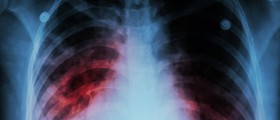

Suspicious Densities On The Lungs: A Sign Of Lung Cancer?

An irregularity on an X-ray may make you think that a diagnosis of cancer is imminent but there is more to it. There are specific characteristics and markers that can point to one form of cancer to another or may even suggest cancer is not likely at all.